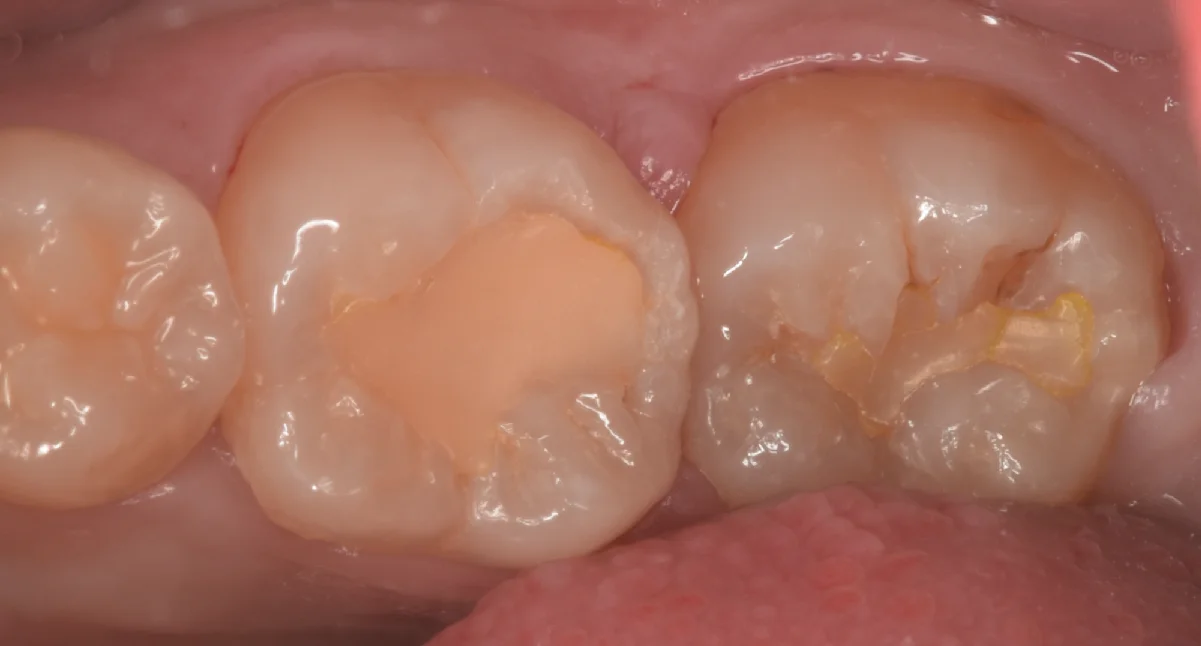

まずは術前からです。

画面中央の白い詰め物の部分と右側の白い詰め物の部分が今回治療する部位になります。

数年前に治療をしたとのことですが、材料が相当に劣化していますね。